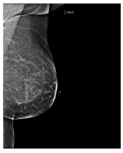

| ACR Class | Feature | Tissues Proportion | Example |

|---|---|---|---|

| B | Fibro-glandular | 25–50% dense tissue | ![]() |